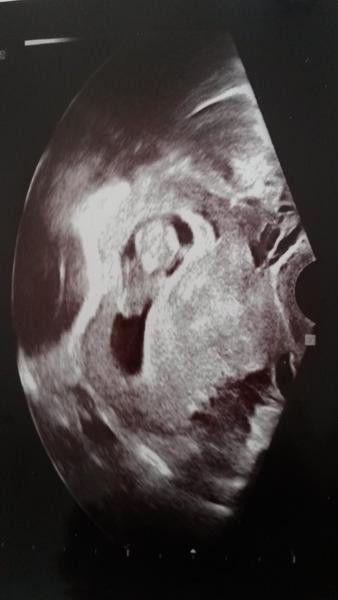

Baby, takto vyzerame my. Krpcek dokonca kopol nozickou na sone, tak som sa rozcitila 🙂🙂🙂

Kocky, ked pozeram vase sona, tak vidim, ze mate kopec plodovej vody. Nase mimi mi pride take stiesnene...myslite si, ze to moze byt tym, ze mi bolo v poslednej dobe moc zle a ani pit som poriadne nemohla?